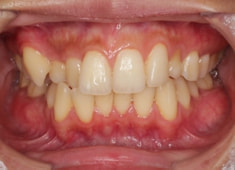

左上3番埋伏歯

治療法:フルパッシブブラケット:T21

治療後(2年後)